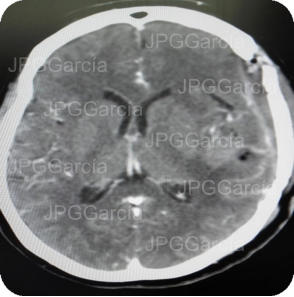

Resultado de tomografía craneal postquirúrgica en donde se observa drenaje del absceso cerebral